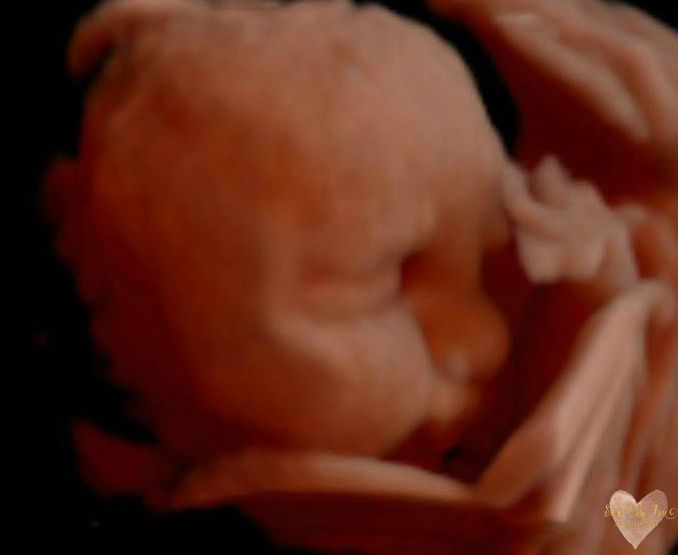

3D/4D/5D Ultrasound Gallery

Take a peek at our Photo Gallery. All of our 2D, 3D, 4D, HD elective ultrasound images are truly ours. They come directly off our machine from our highly trained staff. We can start getting great 3D/4D images as early as 10 weeks!